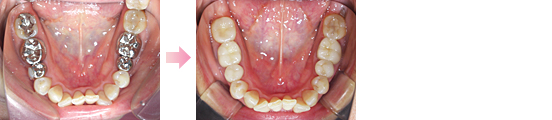

症例2 ・・・来院回数2回で、下の歯2から2を、講演10日後に控えた患者様からのご要望にお答えしました・・・。

一日で行っております。歯は削っておりません・・・。